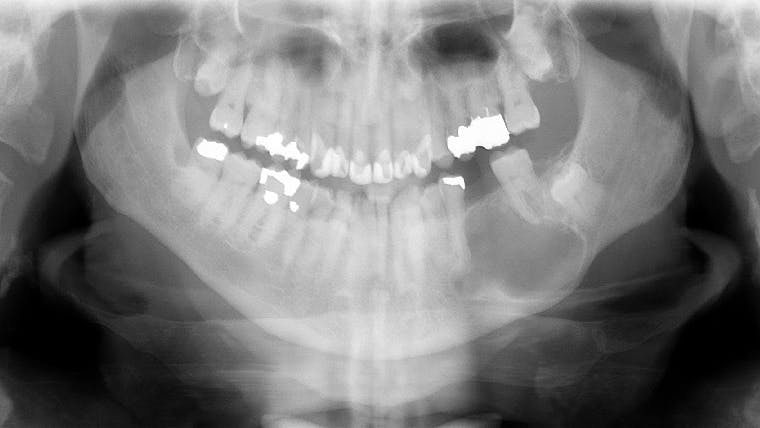

A healthy 66-year-old white male presented to the clinic as a new patient, having not seen a dentist in about six years. In the course of an otherwise normal cleaning, exam, and routine radiography, a large radiolucency was found in the left mid-body of the mandible. The patient denied any pain in the area, hadn’t noticed any new swelling, and denied paresthesia of his left inferior alveolar nerve (V3). His exam showed he was missing tooth no. 19. He explained that it was extracted by his previous dentist about seven years ago.

The rest of his dental exam was normal; there were no oral lesions or vestibular swelling. Extraorally there was no visual or palpable swelling in the area, and no cervical lymphadenopathy.

Common things are common. The lesion the patient presented with should be highly suspicious for a residual cyst. A residual cyst is simply a periapical cyst that was not properly removed at the time the tooth was treated, and in this case during the extraction of tooth No. 19. The cyst remained in the mandible following the extraction, and for the following six years grew slowly and painlessly without the patient being aware of it.

Treatment for the cyst outlined in this case first involved an incisional biopsy for definitive diagnosis of the lesion. Once the diagnosis of residual cyst was obtained, the patient underwent a second clinical procedure to remove the entirety of the cyst through an intraoral incision with enucleation and curettage. All walls of the mandible remained following removal; therefore, near-complete bony fill after healing should be seen. Recurrence of the lesion is extremely rare, so follow-up with normal dental visits and routine radiography should be sufficient.